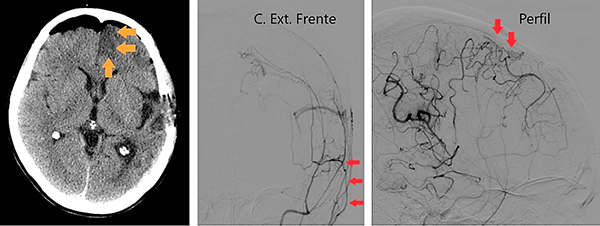

Caso clínico # 2: LD femenino de 51 años con antecedente de tabaquismo e hipertensión arterial, estudiada por deterioro cognitivo de varios meses de evolución. La RMN y ARM evidencia atrofia de hemisferio cerebral izquierdo con hiperintensidad periventricular y disminución franca del calibre de las arterias cerebral anterior y media izquierda con desarrollo de los vasos de MM (Fig. 3). La ADC muestra el stop de la arteria carótida interna izquierda distal y ausencia del origen de las cerebrales anterior y media, buen desarrollo de los vasos de MM y aporte de vasos meníngeos y etmoidales correspondiente a un grado 4 de Suzuki (Fig. 4). Se realizó una revascularización cerebral combinada: un bpTS izquierdo más EDMS y, para aumentar la perfusión en territorio de ambas arterias cerebrales anteriores, un EGPS bifrontal. En la TAC postoperatoria se evidenció un infarto fronto-polar mesial sin repercusión clínica. La ADC postoperatoria diferida evidencia una buena revascularización en los territorios de las arterias cerebral anterior y media a partir del bpTS y la doble sinangiosis (Fig. 5).

Fig. 4 Caso clínico # 2. ADC preoperatoria con compromiso bilateral de las arterias carótidas supraclinoidea mayor a izquierda, vasos de MM y presencia de anastomosis leptomeníngeas. Nótese el signo de la botella de champagne en el origen de la arteria carótida interna cervical, presente en los MM avanzados. Corresponde a un grado 4 de Suzuki

Fig. 5 Caso clínico # 2. Postoperatorio. A la izquierda una TAC con pequeño infarto frontomesial. La imagen del centro es una ADC de frente que muestra el bpTS con muy buena perfusión cerebral. La imagen de la derecha es la ADC de perfil que muestra una buena perfusión cerebral a partir de la EGPS bifrontal